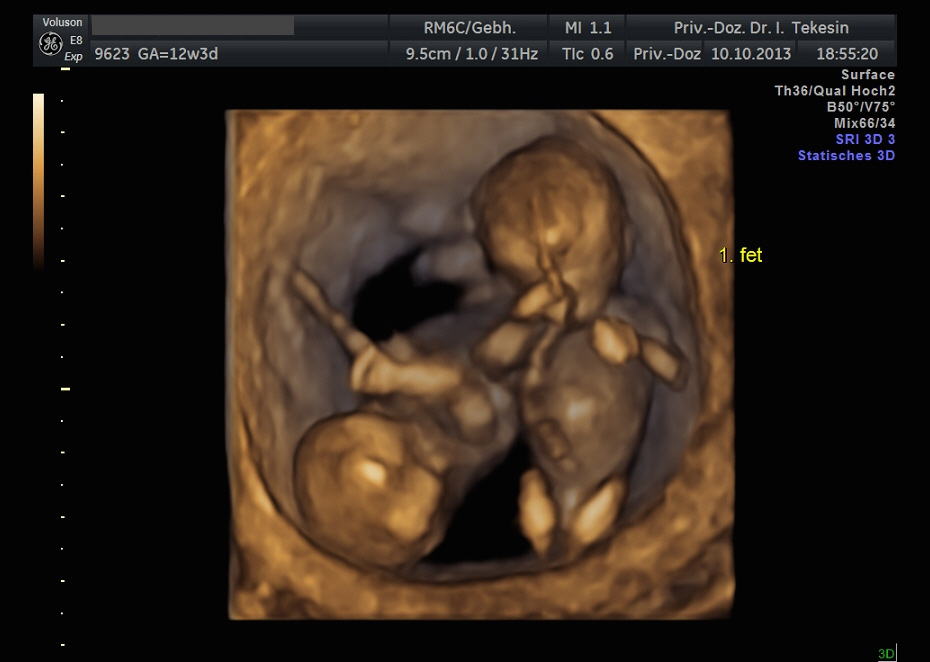

Dichoriale Zwillinge in der 11. Woche (3D-Darstellung)

Monochoriale Zwillinge in der 13. Woche (3D-Darstellung)